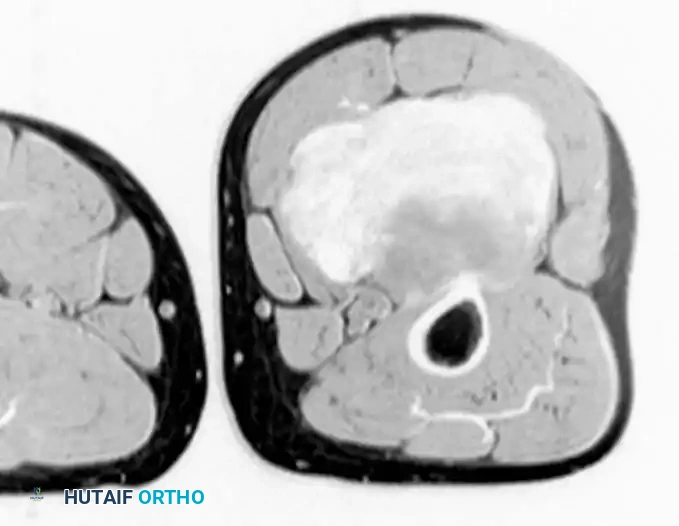

Imaging:

MRI is highly specific for well-differentiated variants, demonstrating fat signal intensity (bright on T1, suppresses on STIR/Fat-Sat) with thick, nodular septations.

T1-weighted MRI of a well-differentiated liposarcoma (atypical lipoma) of the thigh.

Contrast-enhanced, fat-suppressed axial MRI of the same lesion. Note the multiple thick, enhancing septa distinguishing it from a benign lipoma.